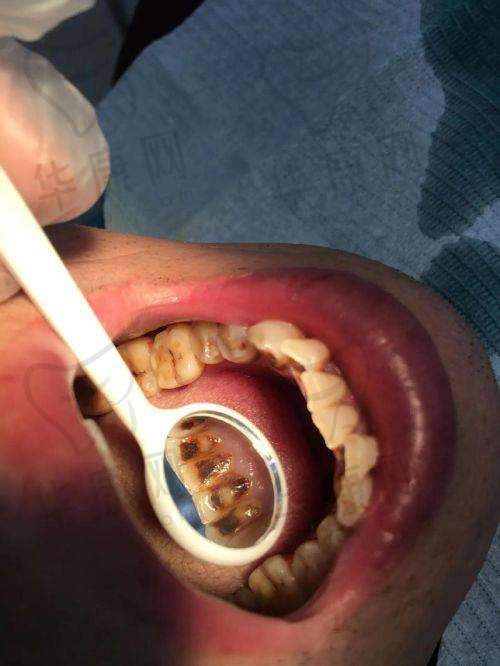

许多在宜春袁州春城口腔进行过喷砂洁牙的患者都反馈成效显著。经过喷砂洁牙后,牙齿变得更加洁白干净,口气也清新了许多。而且,由于医生操作熟练,整个洁牙过程没有明显的疼痛感。在口碑方面,该医院也获得了患者的广泛认可。像在一些口腔相关的论坛和平台上,经常能看到患者对宜春袁州春城口腔喷砂洁牙的好评,称赞其价格实惠、服务周到、成效好。